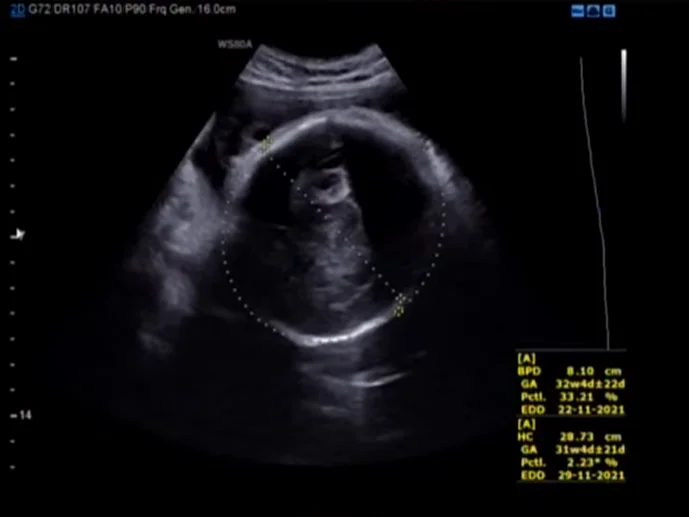

Thai chậm tăng trưởng chọn lọc trong sinh đôi (Selective Fetal Growth Restriction - sFGR)